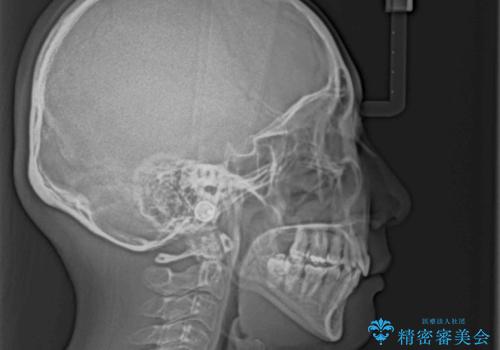

- 八重歯と上下前歯のでこぼこを気にして来院された患者様です。

上下前歯部叢生のスペース獲得のため、上下顎左右小臼歯各1歯(計4本)を抜歯して、ワイヤー装置にて矯正治療を行うこととしました。

上下の正中位置が大きくずれていたため、上下正中が合わないまま終了することが予想されましたが、思っていた以上にスムーズに歯が移動し、満足いただける仕上がりとなりました。